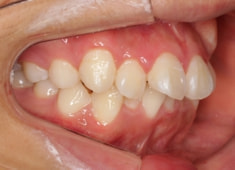

治療前